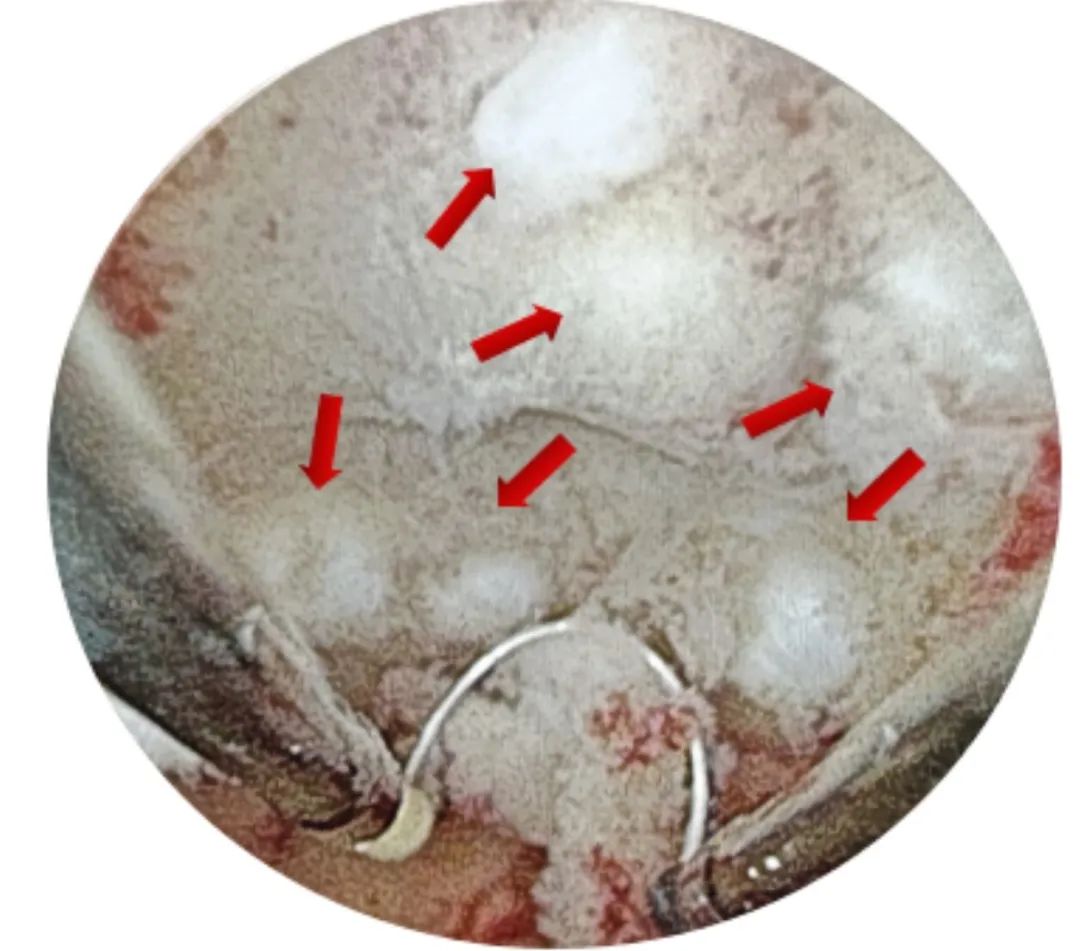

术中,宫腔检查镜进入宫腔的一刻,发现宫腔里密布大小不一的子宫肌瘤(见下图),均为I、II型,宫腔形态失常,且合并子宫憩室,妇二科专家团队运用娴熟的手术技巧,逐一切除可见瘤体,切除过程中不断发现隐匿于肌层的瘤体,恢复宫腔正常形态,最大程度上保护了子宫内膜,共切除瘤体23枚。患者术后即可下地活动,无阴道出血,术后3天康复出院。